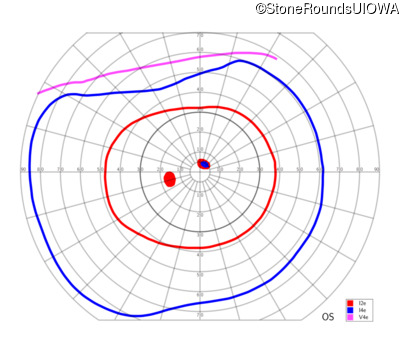

AR Stargardt Disease (IIA)

AR Stargardt Disease (IIA)

This 11 year old female first had difficulty seeing the blackboard at age 8. Later, she developed some photophobia.